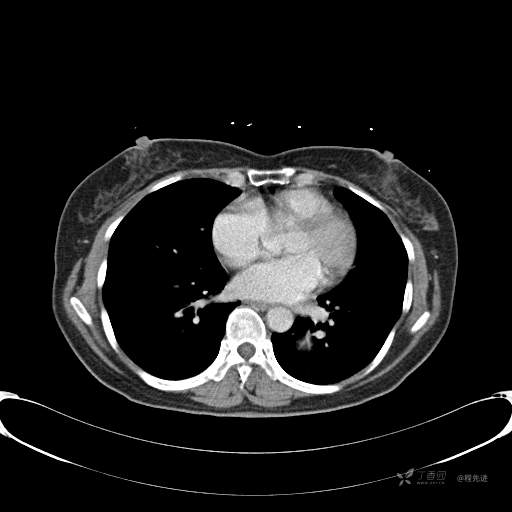

CT增强

平扫CT值约40HU(未上传图像),增强后动脉期CT值约70HU,静脉期CT值约97HU。